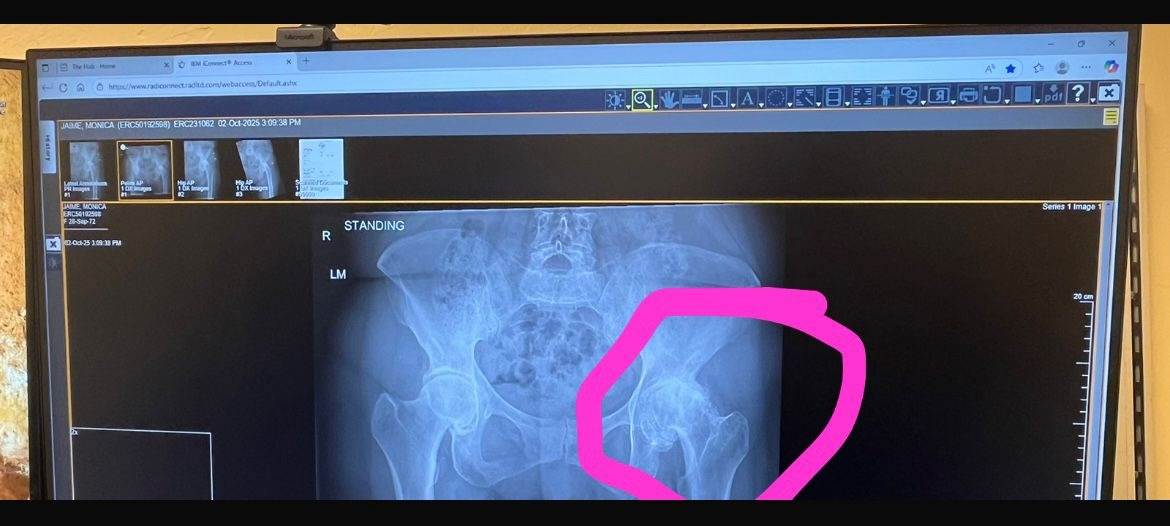

But unfortunately, she is in need of emergency hip surgery. She needs this done as soon as possible as she is at risk of infection if she does not get the surgery soon. She is someone who loves to dance, and if it is not done soon, she will end up in a wheelchair for the rest of her life. She needs all the help she can get. She is aware the holidays are approaching, but Monica and her family would be truly grateful for any donations.

Pero, lamentablemente, necesita una cirugía de cadera de emergencia. Necesita que esto se haga lo antes posible, ya que corre riesgo de infección si no recibe la cirugía pronto. A ella le encanta bailar, y si no se realiza la operación, podría terminar en una silla de ruedas por el resto de su vida. Necesita toda la ayuda que pueda recibir. Sabemos que se acercan los días festivos, pero Mónica y su familia estarían verdaderamente agradecidos por cualquier donación.